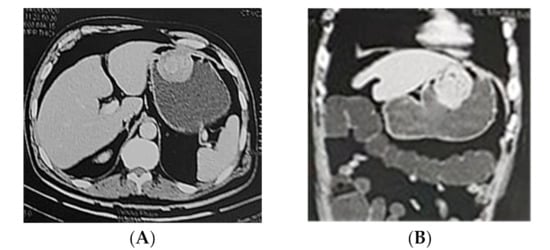

2.1.3. CT Enterocolongraphy

3.1. CT Enterocolongraphy